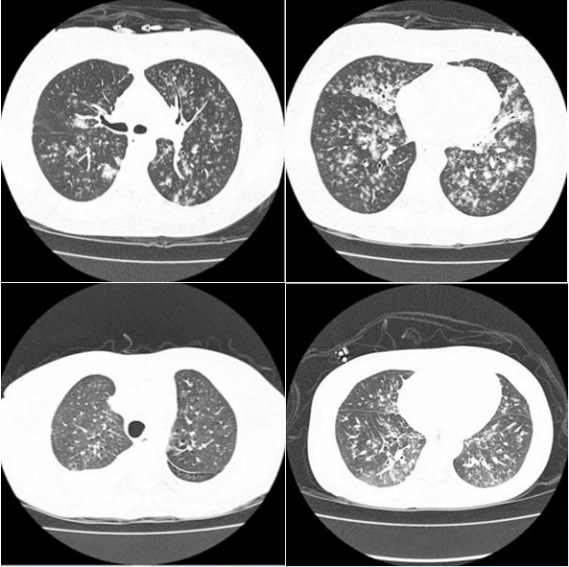

图源:AJR Am J Roentgenol, 2013, 201(3):550-554.另有研究总结了6例造血干细胞移植患者影像学特点,代表免疫受损严重患者的影像特点,其中多发小结节(最常见)(<5 mm为主,也有5~10 mm结节或>1 cm结节),支气管周围分布,外周分布的磨玻璃密度增高影、含支气管充气征的实变(1/2出现)(图4)。

图4. 造血干细胞移植患者影像学表现

图源:Clin Infect Dis, 2009, 48(7):905-909.PCR是PIV的首选检测方法,通常可用鼻咽拭子或肺泡灌洗液(BALF),PCR阳性可确诊。快速抗原检测敏感性低,PIV培养和血清学未广泛开展,而且周转时间长。